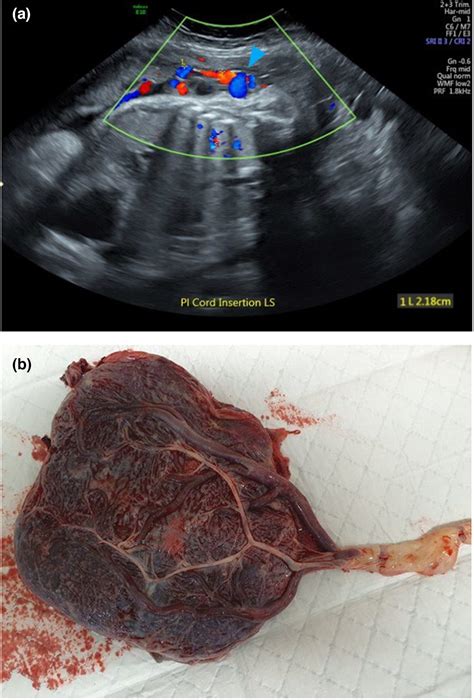

Diagnosis of Marginal Cord Insertion

Marginal cord insertion is typically diagnosed during routine prenatal ultrasounds. Ultrasound imaging allows healthcare providers to visualize the placenta and the umbilical cord, determining the location of the cord insertion. Early detection is crucial for monitoring the pregnancy and ensuring the best possible outcomes.

• marginal cord insertion on ultrasound